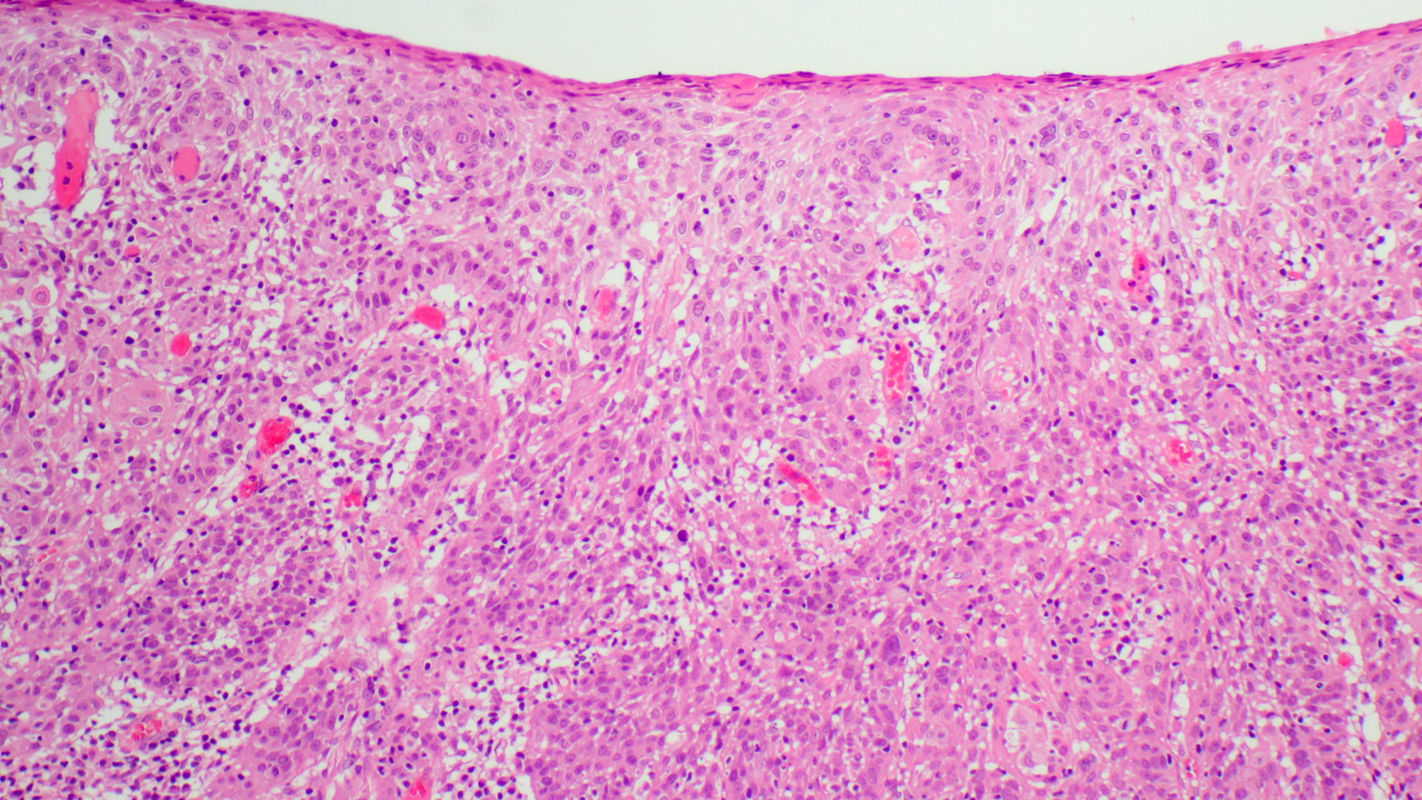

H&E stain of tissue sampled by loop biopsy shows atypical cells that have penetrated the basement membrane and infiltrated the stroma. Blood vessels are clearly visible among the strands of tumor cells and extend almost to the tissue surface.

The diagnosis is undifferentiated invasive squamous cell carcinoma. Following laparoscopic sentinel lymphadenectomy and radical vaginal trachelectomy, the disease was finally staged as pT1b1 pN0 (0/2 sn) G3 L0 V0 Pn0.